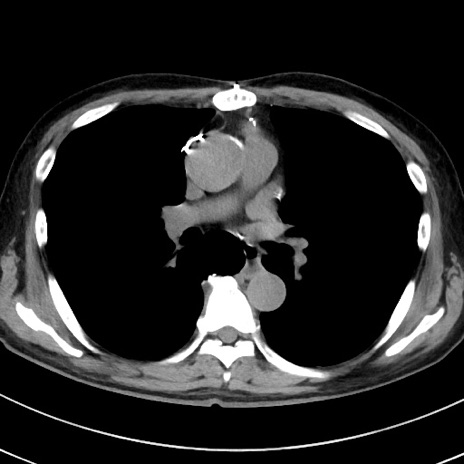

症例38(横断像)

【症例】70歳代 男性

【主訴】腹痛・嘔吐

【現病歴】昨晩より、嘔吐・腹痛あり。今朝になっても嘔吐あり。来院。

【既往歴】心臓バイパス手術、開腹胆摘、腸閉塞

【身体所見】BP 107/71mmHg、HR 116/min、腹部:平坦、軟、下腹部に軽度圧痛あり。反跳痛なし。

【データ】WBC 15100、CRP 0.32